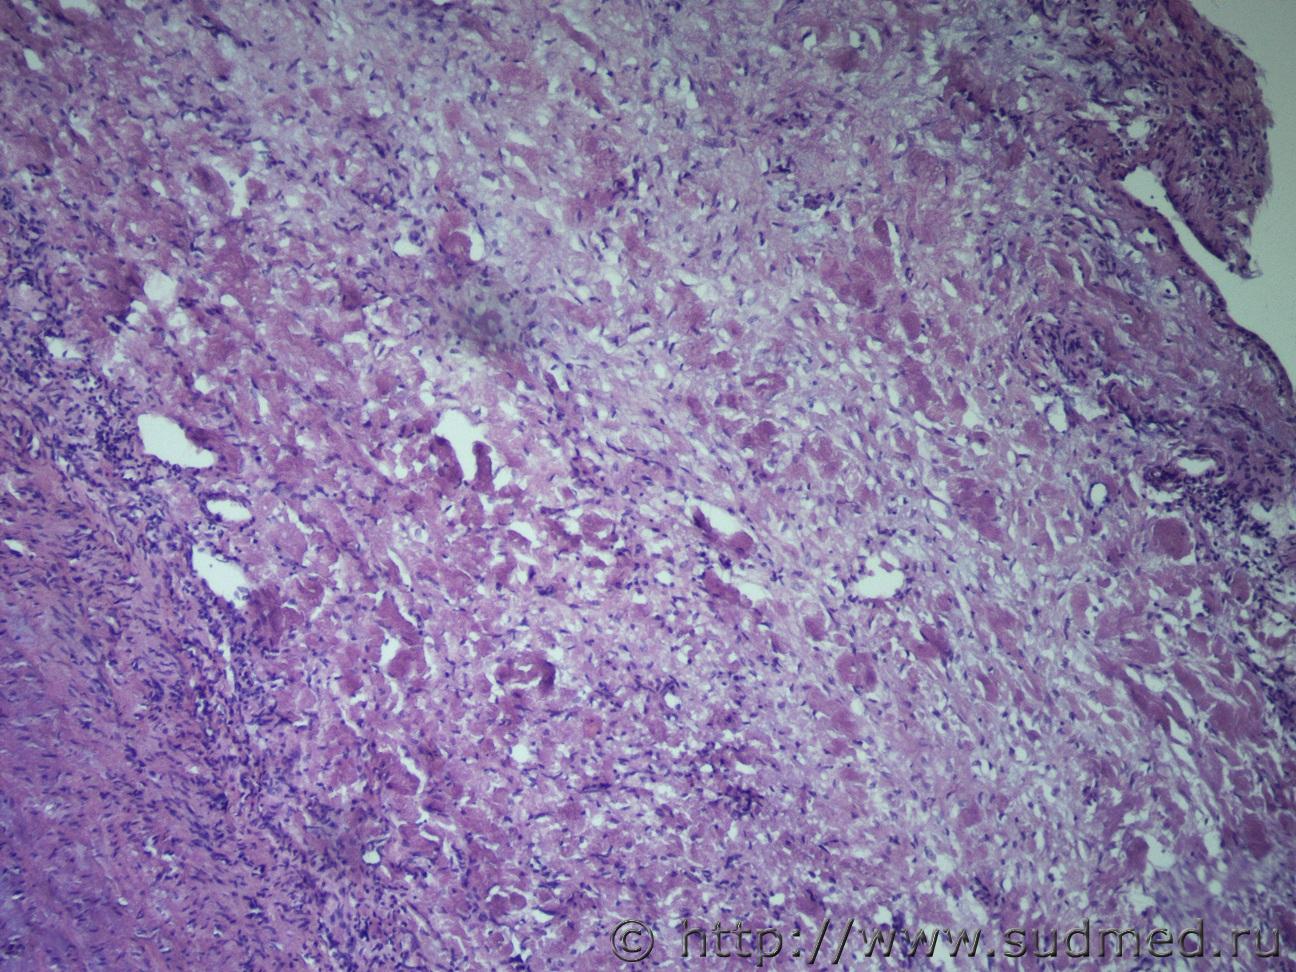

Ув. коллеги, нужна помощь. Жен 33 года, причина смерти ТЭЛА. Находка на секции образование в ветви легочного ствола. Судебная медицина - Прикрепленное изображение Судебная медицина - Прикрепленное изображениеСудебная медицина - Прикрепленное изображениеСудебная медицина - Прикрепленное изображениеСудебная медицина - Прикрепленное изображение

Макро фотографии к сожалению нет. Был фрагмент легочного ствола с бифуркацией, один сосуд с обычными стенками, макро без изменений, в второй неравномерно утолщен, как бы часть сосудистой стенки обычная, а часть утолщена и частично выпирала в просвет.

Эндотелизированный и реканализованный тромб трудно с чем-либо спутать. Теперь надо двигаться дальше: катамнез, причина, источник ТЭЛА и т.д. К примеру, при АФС ответ очевиден, а при "ТЭЛА" вследствие патологии ЛА - думать о сосудистом процессе.